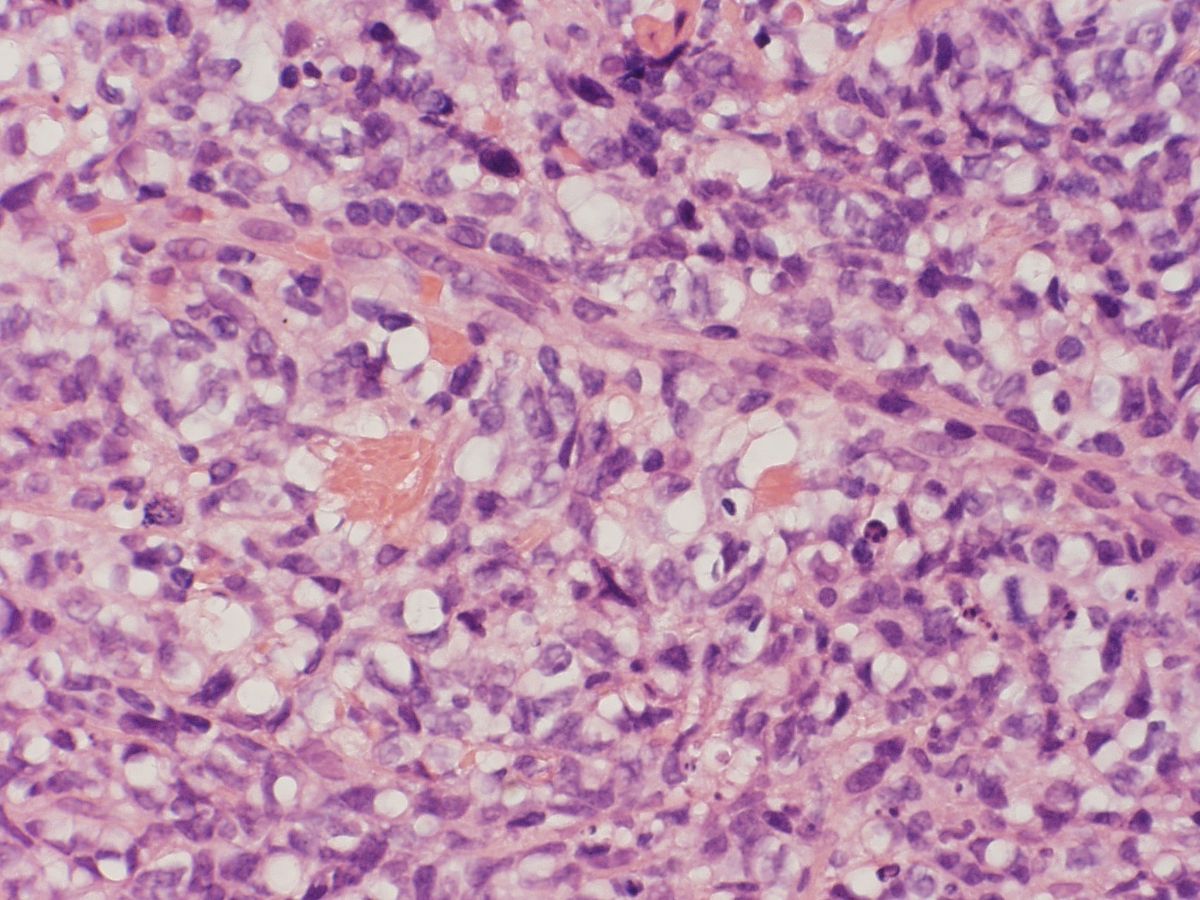

PA:

Epidermis geen afwijkingen. In de oppervlakkige dermis bevindt zich een dicht infiltraat van atypische lymfoïde cellen. De lymfoïde cellen tonen vergrote, blazige, gedenteerde kernen, meerdere mitose-figuren zijn zichtbaar. Tussen het infiltraat en de epidermis bevindt zich een vrije zone. De tumorcellen kleuren positief aan voor CD79a, en CD20 en negatief voor CD3. Met moleculair pathologisch onderzoek kan een clonale B-cel populatie worden aangetoond.

Dit type cutaan lymfoom komt vooral voor bij oudere patiënten (>70 jaar). Klinisch ziet men één of meerdere paarsrode tumoren op één of beide (onder)benen. Bij circa 10% elders op het lichaam. Histologie: diffuus infiltraat van centroblasten en immunoblasten, bcl-2, Mum-1 en Fox-P1 positief. Zie ook de ingescande PA-coupe van de afdeling pathologie van de University of Toronto.